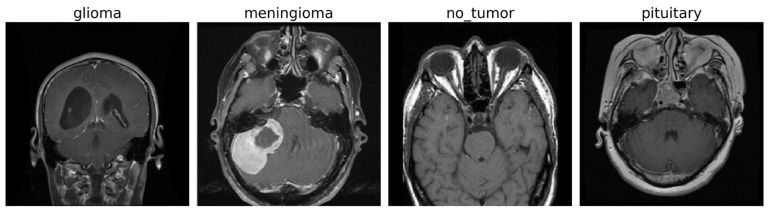

背景:从MRI扫描中准确分类脑肿瘤亚型对于及时诊断至关重要,然而对大型数据集的手动注释仍然是令人难以接受的劳动密集型。方法:我们提出了SSPLNet(半监督伪标记网络),这是一个双分支深度学习框架,它将置信度引导的迭代伪标记与深度特征融合协同起来,从而在数据受限的临床环境中实现基于mri的鲁棒肿瘤分类。SSPLNet集成了自定义卷积神经网络(CNN)和预训练的ResNet50模型,使用自适应置信阈值(τ = 0.98→0.95→0.90)训练半监督,迭代地改进未标记MRI扫描的伪标签。两个分支的特征表示通过密集网络融合,将局部纹理模式与层次深度特征相结合。结果:SSPLNet在标记-未标记数据分割(90:10至10:90)中实现了最先进的准确性,在极低标签方案(10:90)中优于监督基线,自定义CNN高达5.34%,ResNet50高达5.58%。该框架减少了对注释的依赖,并且在40%未标记数据的情况下保持了98.17%的诊断准确性,证明了其在资源有限的医疗保健环境中可扩展部署的可行性。结论:SSPLNet性能的统计评价和鲁棒性分析证实了SSPLNet较低的错误率并非偶然。bootstrap结果还证实,SSPLNet报告的准确性落在抽样分布的95% CI范围内。

Background: The accurate classification of brain tumor subtypes from MRI scans is critical for timely diagnosis, yet the manual annotation of large datasets remains prohibitively labor-intensive. Method: We present SSPLNet (Semi-Supervised Pseudo-Labeling Network), a dual-branch deep learning framework that synergizes confidence-guided iterative pseudo-labelling with deep feature fusion to enable robust MRI-based tumor classification in data-constrained clinical environments. SSPLNet integrates a custom convolutional neural network (CNN) and a pretrained ResNet50 model, trained semi-supervised using adaptive confidence thresholds (τ = 0.98 → 0.95 → 0.90) to iteratively refine pseudo-labels for unlabelled MRI scans. Feature representations from both branches are fused via a dense network, combining localized texture patterns with hierarchical deep features. Results: SSPLNet achieves state-of-the-art accuracy across labelled-unlabelled data splits (90:10 to 10:90), outperforming supervised baselines in extreme low-label regimes (10:90) by up to 5.34% from Custom CNN and 5.58% from ResNet50. The framework reduces annotation dependence and with 40% unlabeled data maintains 98.17% diagnostic accuracy, demonstrating its viability for scalable deployment in resource-limited healthcare settings. Conclusions: Statistical Evaluation and Robustness Analysis of SSPLNet Performance confirms that SSPLNet's lower error rate is not due to chance. The bootstrap results also confirm that SSPLNet's reported accuracy falls well within the 95% CI of the sampling distribution.